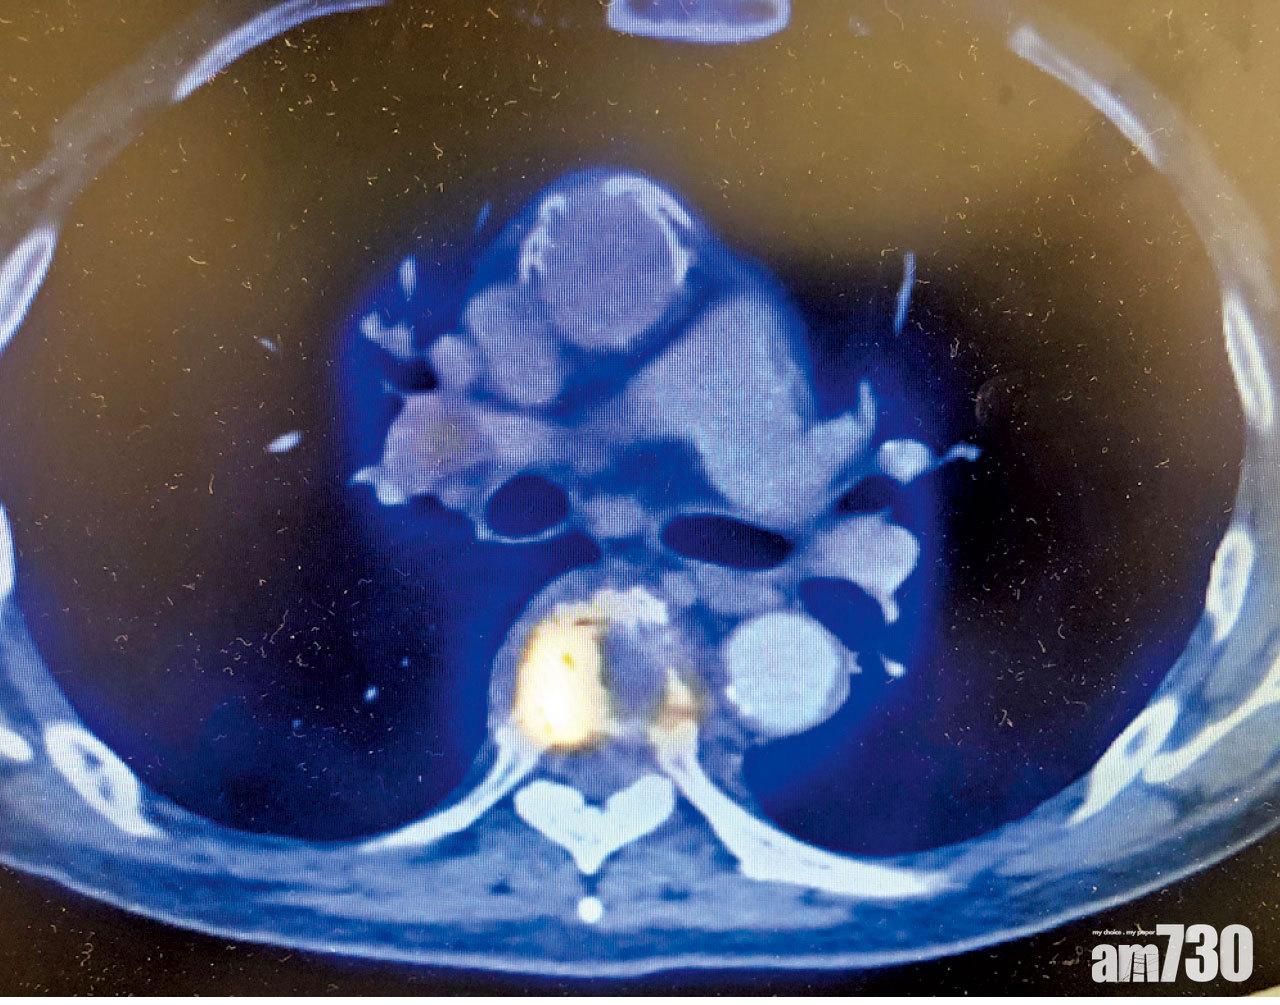

去年確診的一位69歲男性晚期肺癌患者,腫瘤已輕微破壞了其脊椎,PD-L1蛋白水平雖高,但當時免疫治療沒有安全網,又不適合標靶而選擇化療。到今年中病情轉差,沒錢用二線免疫治療,惟有轉用另一化療藥,不過效果不大,及後腫瘤更壓住脊椎,帶來嚴重背痛和腳痹,不能走路。為避免癱瘓緊急做手術固定脊骨,猶幸回復走動能力,不過病情再次惡化的話,又會再次出現癱瘓危機。幸而最後申請到慈善基金,可資助免疫治療頭一年的七成藥費,病情有望好轉。

患者腫瘤壓住脊椎,導致背痛和腳痹。